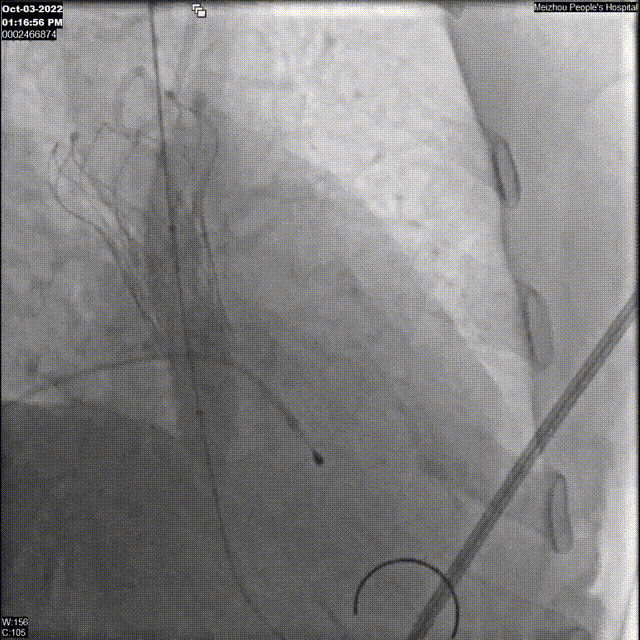

1、左/右冠脉PCI术前影像

2、左/右冠脉PCI术后影像